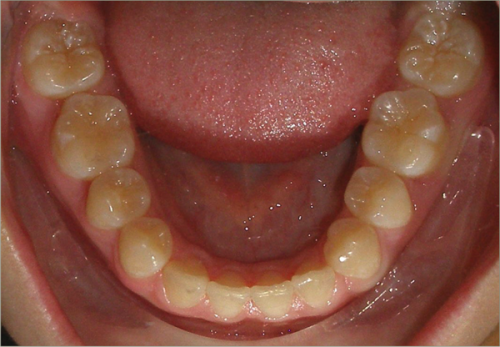

12 year old female:

Diagnosis:

- Missing upper right lateral incisor & lower right cuspid

- Horizontally impacted lower left cuspid

- Peg shaped upper left lateral incisor

Treatment:

- Extraction of impacted lower left cuspid, and peg shaped upper left lateral incisor

- Upper cuspids substituted as laterals

- Full fixed appliances

- 20 months